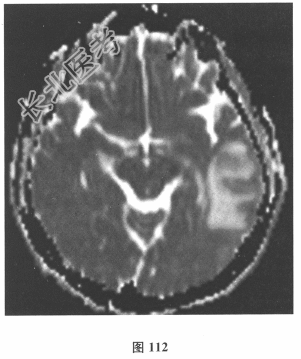

- 简答题2、脑脊液检查:常规、生化均正常,CSF-病毒TORCH(-),抗Hu、Yo、Ri均阴性,OB、MBP正常。血清抗Hu、Yo、Ri均阴性。颅脑MRI显示左颞枕、右顶枕多发长T₁、长T₂信号,Flair高信号,病变累及皮质及皮质下白质,病灶无强化,见图108~图114。)根据颅脑MRI,需要鉴别的疾病应是